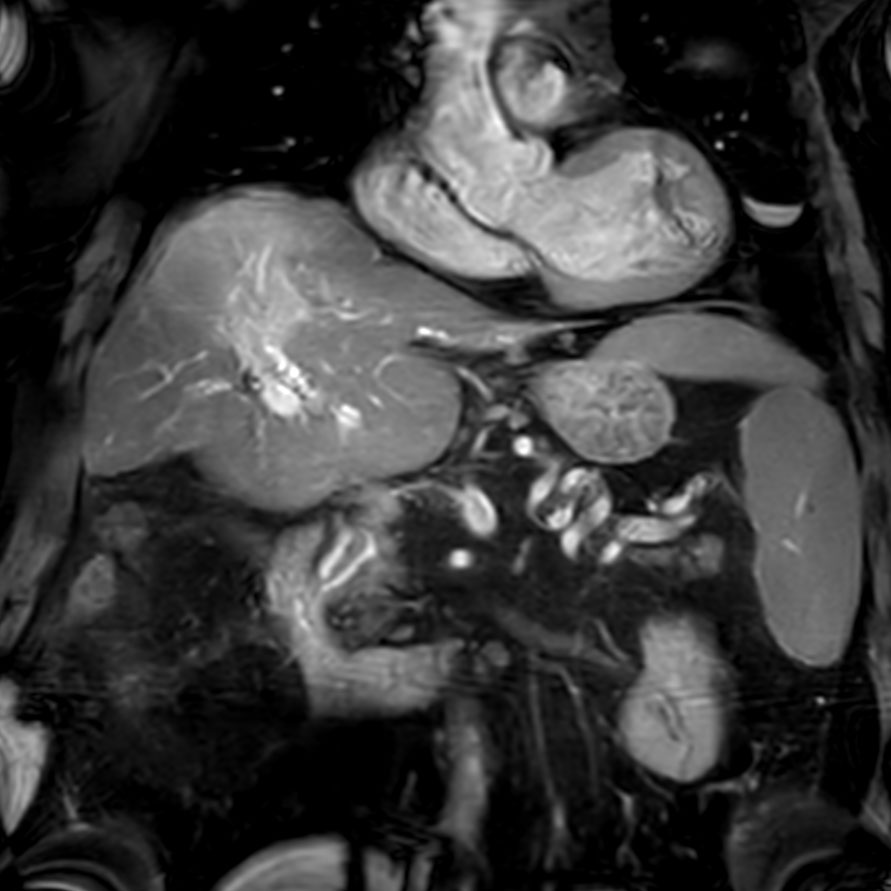

Coronal bTFE SPIR